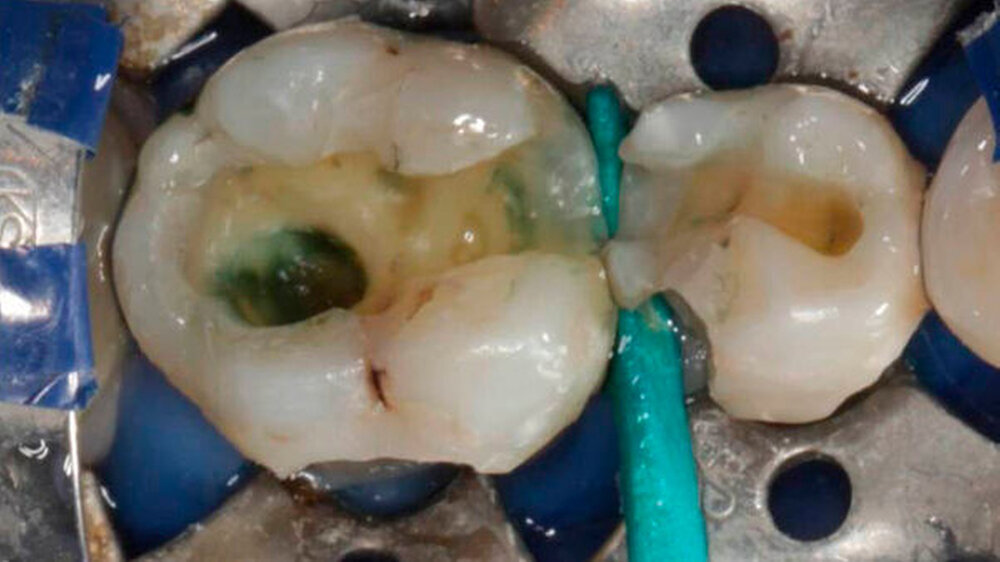

Das Röntgenbild zeigte, dass die Füllungen bei Zahn 45 und 46 nahe an der Pulpakammer lagen. Mit EPT (32/80, 35/80) und thermischen Tests wurde die Pulpavitalität geprüft (normal). Die Diagnose lautete: tiefe Karies. Die Kompositfüllungen wurden daraufhin möglichst substanzschonend ersetzt.

Die Behandlung umfasste zwei Termine (erster: Zahn 46 und 45, zweiter: Zahn 43 und 44). Zur Entfernung der alten Füllungen dienten ein runder und ein zylindrischer Diamantbohrer sowie langsam laufende Hartmetallbohrer und zur Feinbearbeitung der Kavitäten ein Ultraschallinstrument. Nach selektiver Schmelzätzung applizierte man das Adhäsiv XP BOND®. Das Dentin wurde durch SDR ® ersetzt. Dann wurden mit ceram.x one® d3 und e2 jeweils der Rest der Kavität und die Höcker restauriert. Finiert und poliert wurde mit dem Soflex Poliersystem.